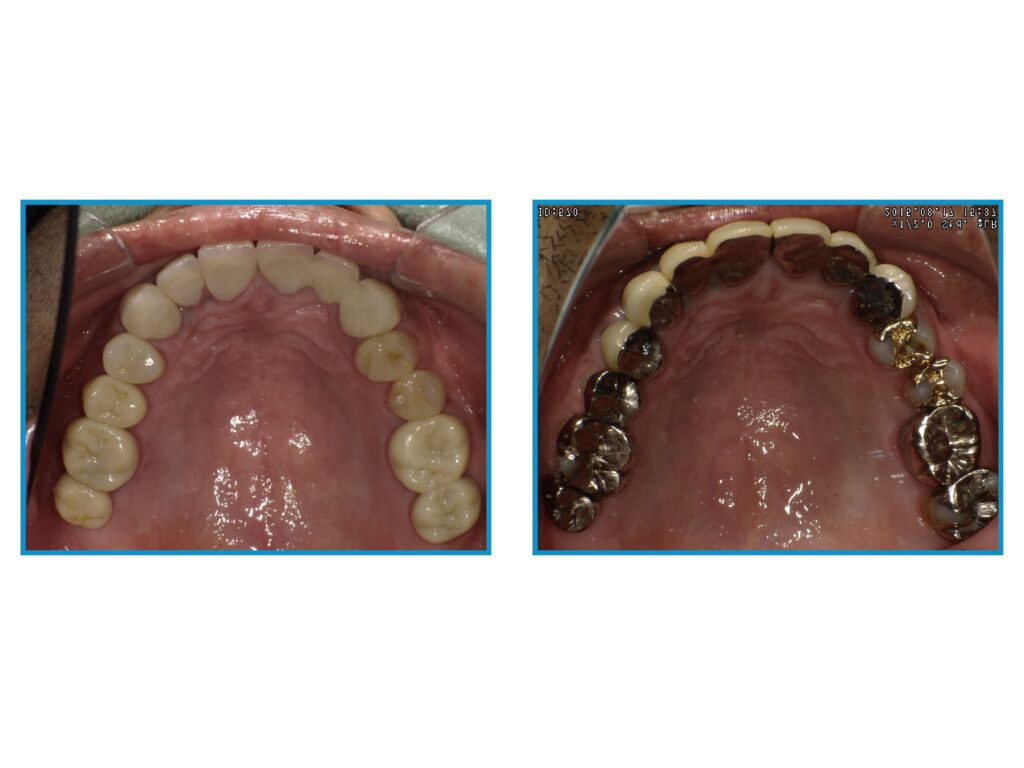

↓メタルフリー治療を受けた患者様